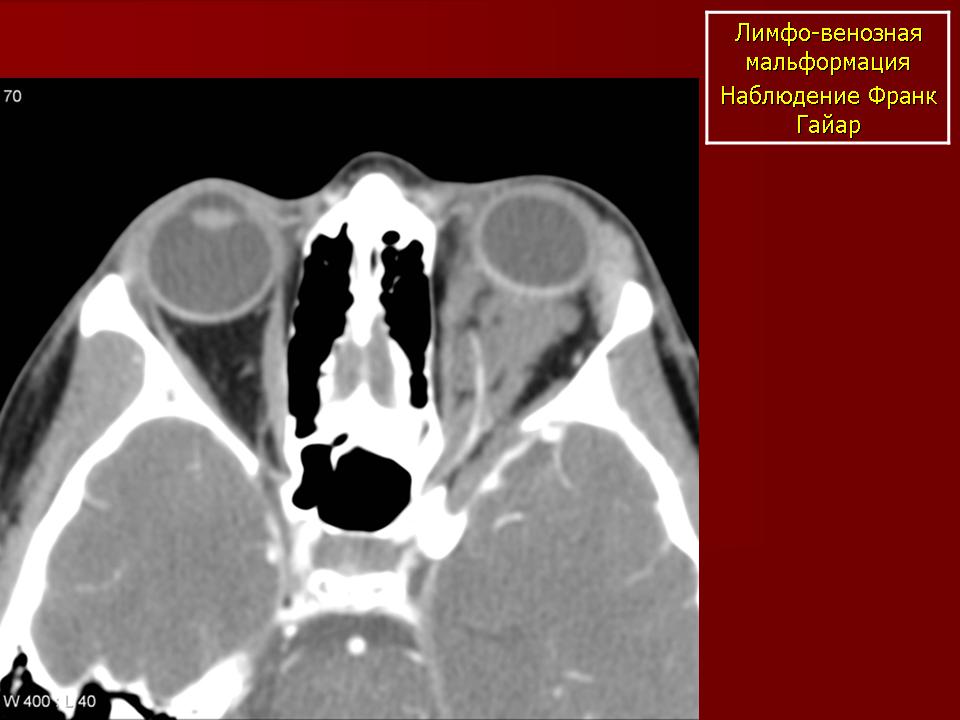

Наиболее типичная черта: выявление уровней жидкости в образовании, за счет спонтанных кровотечений.

Экстраорбитальное (но может быть рапсоалагаться как в канале, так вне его), мультикистозное, мультифокальное объемное образование с неправильным контуром.

Гиперденсное, по плотности сопоставимо с мышечной тканью, негомогенной структуры образование, пересекает анатомические границы. Стенка лимфангиомы вариабельно накапливает КВ. Тип краевого накопления КВ иногда позволяет установить умеренное ремоделирование прилежащей кости. В структуре образования иногда определяются небольшие кальцинаты или флеболиты.